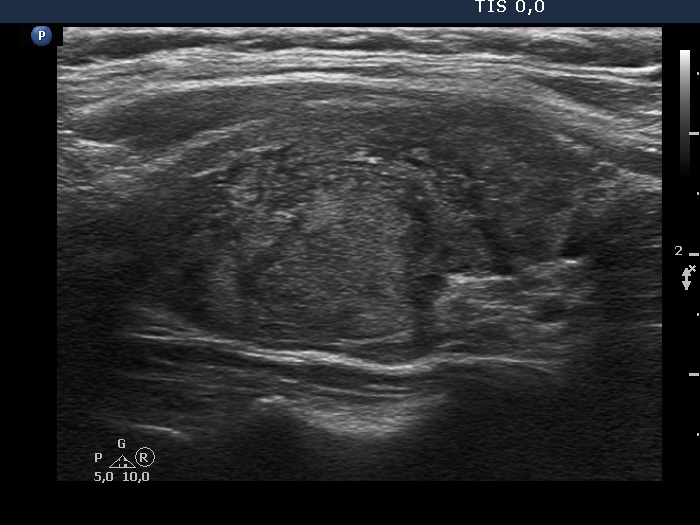

The echogenicity of the nodule - case 2067 (ultrasonographic picture 8)

Left lobe, another longitudinal view.